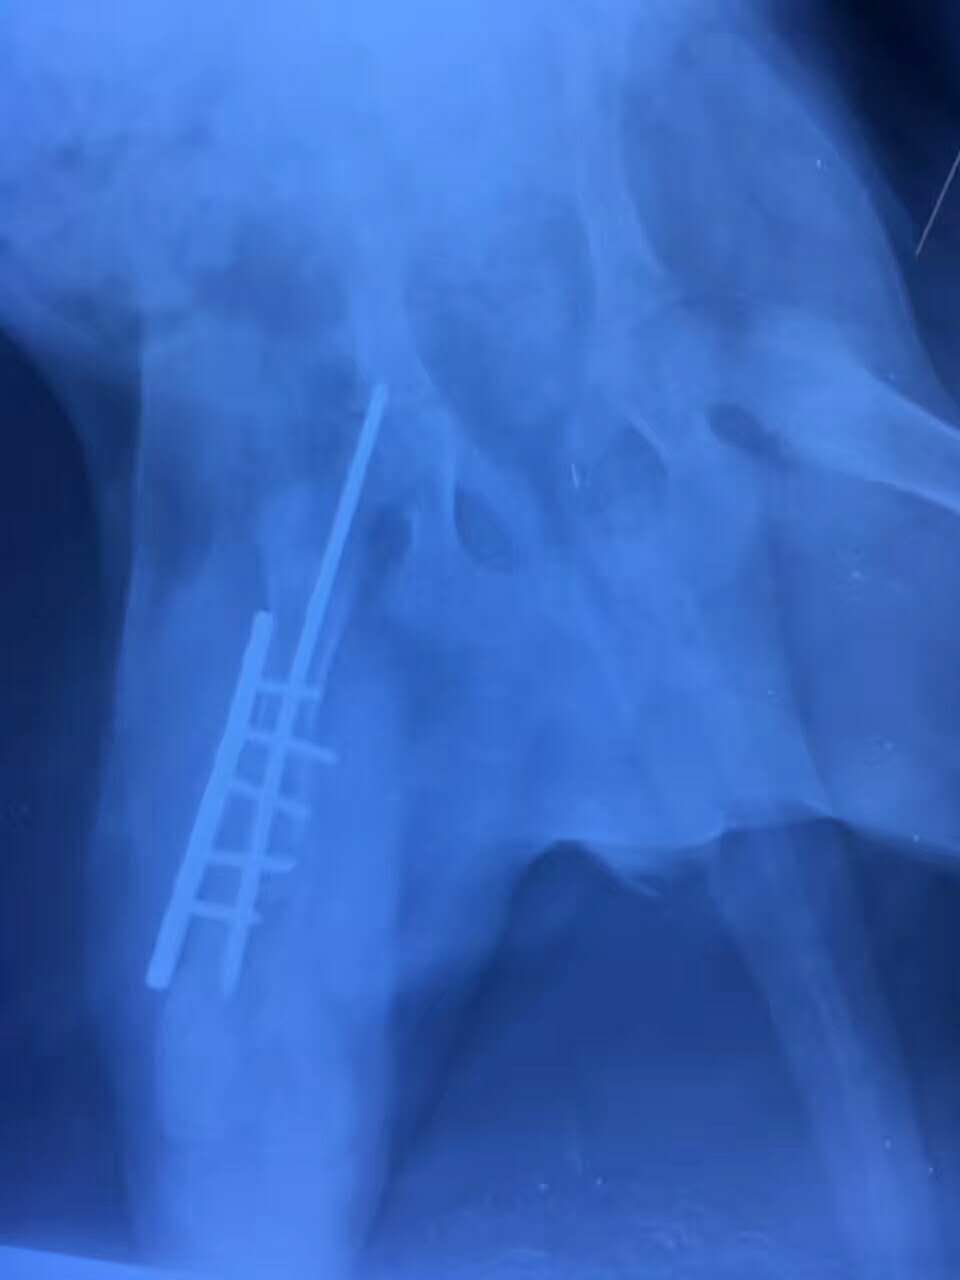

右后肢股骨骨干遠(yuǎn)端骨折手術(shù)

哈士奇骨折夜診:哈士奇 哈哈,從約1米高處跌落,致右后肢股骨骨干偏遠(yuǎn)端骨折,主人連夜送醫(yī),醫(yī)院當(dāng)晚手術(shù),手術(shù)非常順利,狗狗已蘇醒。我們的宗旨是把寵物的健康和生命放在*位,真正24小時接診,洛陽狗博仕寵物醫(yī)院。